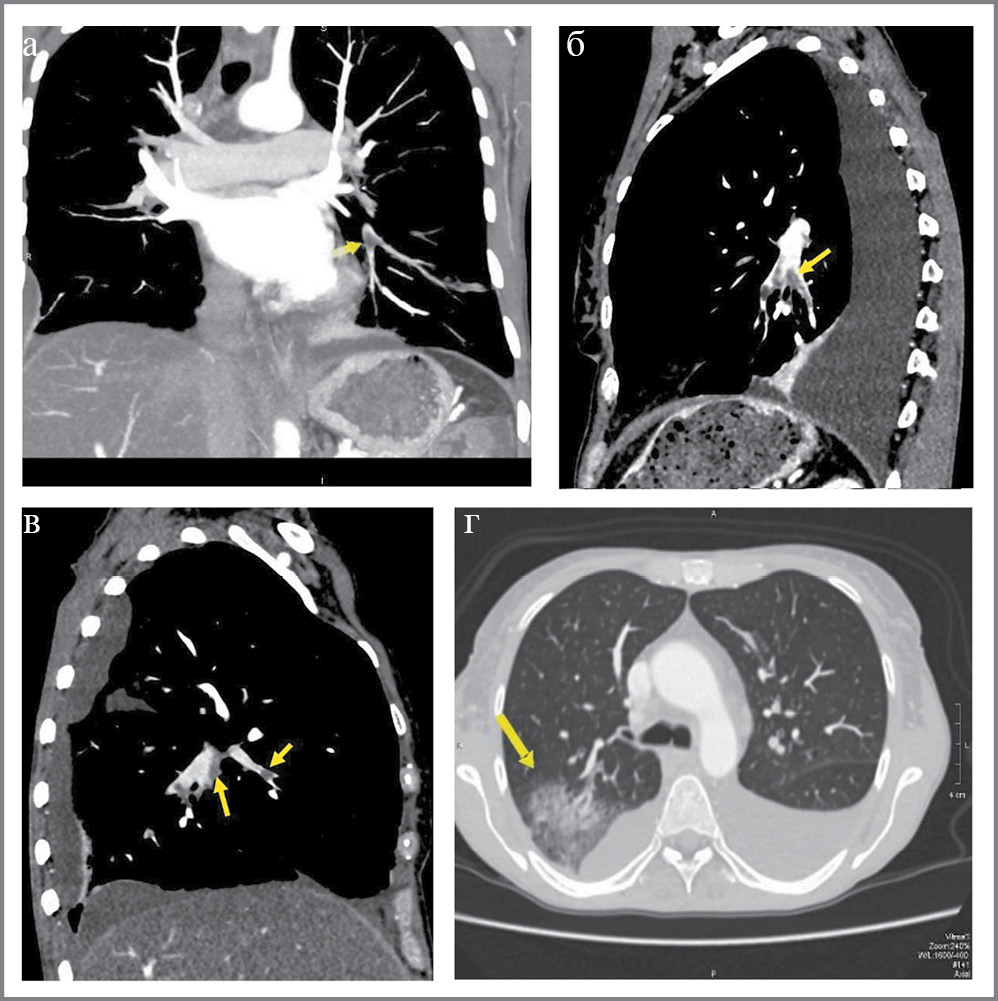

При компьютерной томографической (КТ) ангиопульмонографии обнаружены признаки тромбоэмболии ветвей легочной артерии с развитием инфаркт-пневмонии; двусторонний гидроторакс с признаками осумкования справа; центрилобулярная эмфизема легких (рис. 3).

Рис. 3. КТ-ангиопульмонография: тромбоэмболия ветвей легочной артерии с развитием инфаркт-пневмонии:

а – мультипланарная реконструкция, корональная плоскость, дефект контрастирования (тромбоэмбол) в просвете левой нижнедолевой легочной артерии и ее сегментарных ветвях (стрелка); б – мультипланарная реконструкция, сагиттальная плоскость, дефект контрастирования (тромбоэмбол) в просвете левой нижнедолевой легочной артерии и ее ветвей (стрелка); в – мультипланарная реконструкция, сагиттальная плоскость, дефект контрастирования (тромбоэмбол) в просвете правой нижнедолевой легочной артерии и ее ветвей (стрелка); г – аксиальная плоскость, легочное электронное окно, зона консолидации легочной ткани – инфаркт-пневмония (стрелка) и дефект контрастирования (частично реканализированный тромбоэмбол) в задней сегментарной ветви верхнедолевой легочной артерии.

Fig. 3. CT-angiopulmonography: thromboembolism of the branches of the pulmonary artery with the development of infarction pneumonia:

a – multiplanar reconstruction, coronal plane, contrast defect (thromboembolism) in the lumen of the left lower lobe pulmonary artery and its segmental branches (arrow); b – multiplanar reconstruction, sagittal plane, contrast defect (thromboembolism) in the lumen of the left inferior lobe pulmonary artery and its branches (arrow); c – multiplanar reconstruction, sagittal plane, contrast defect (thromboembolism) in the lumen of the right lower lobe pulmonary artery and its branches (arrow); d – axial plane, pulmonary electron window, zone of pulmonary tissue consolidation: infarction-pneumonia (arrow) and contrast defect (partially recanalized thromboembolism) in the posterior segmental branch of the upper lobe pulmonary artery.